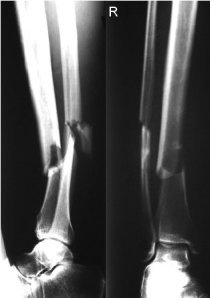

Para finalizar un caso clínico. Veamos como operáis: Accidente tráfico. Fractura de tibia y peroné. Fijaos en el desplazamiento, muy agresivo para los tejidos circundantes: